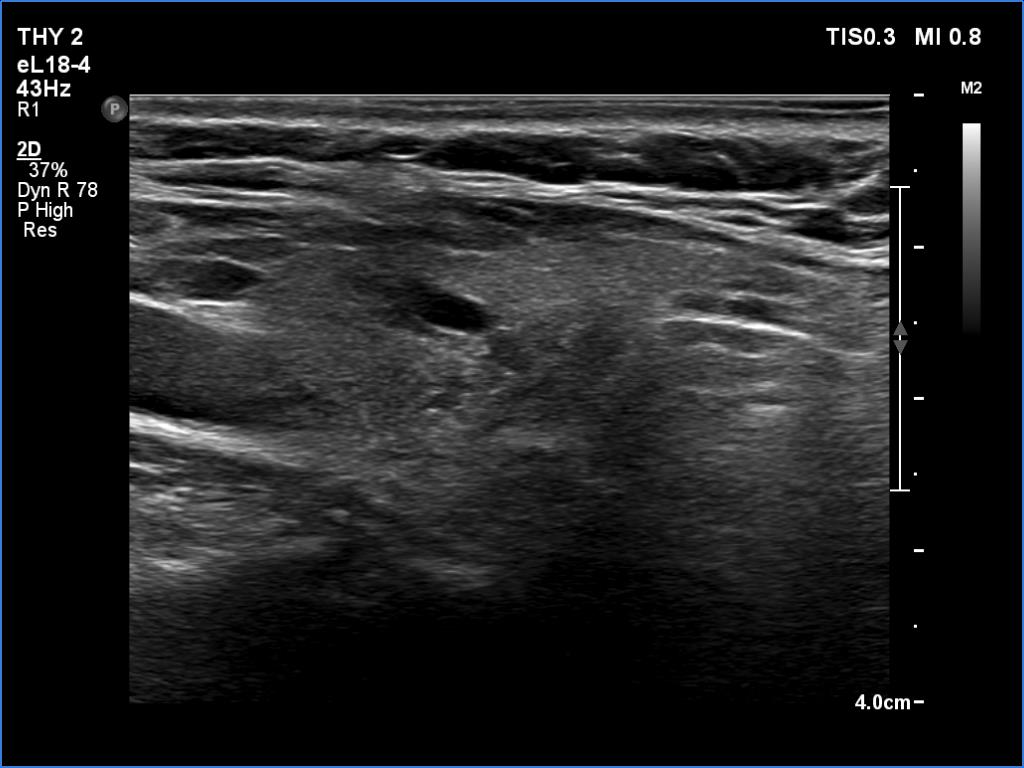

Follow-up examination 5 years (6th row of images):

Clinical presentation: The patient had no complaints.

Palpation: no abnormality.

Functional state: TSH 0.16 mIU/L, FT4 16.7 pM/L on daily 75 microgram levothyroxine.

Ultrasonography: Compared with the last examination, the thyroid was less hypoechoic. The vascularization was decreased.